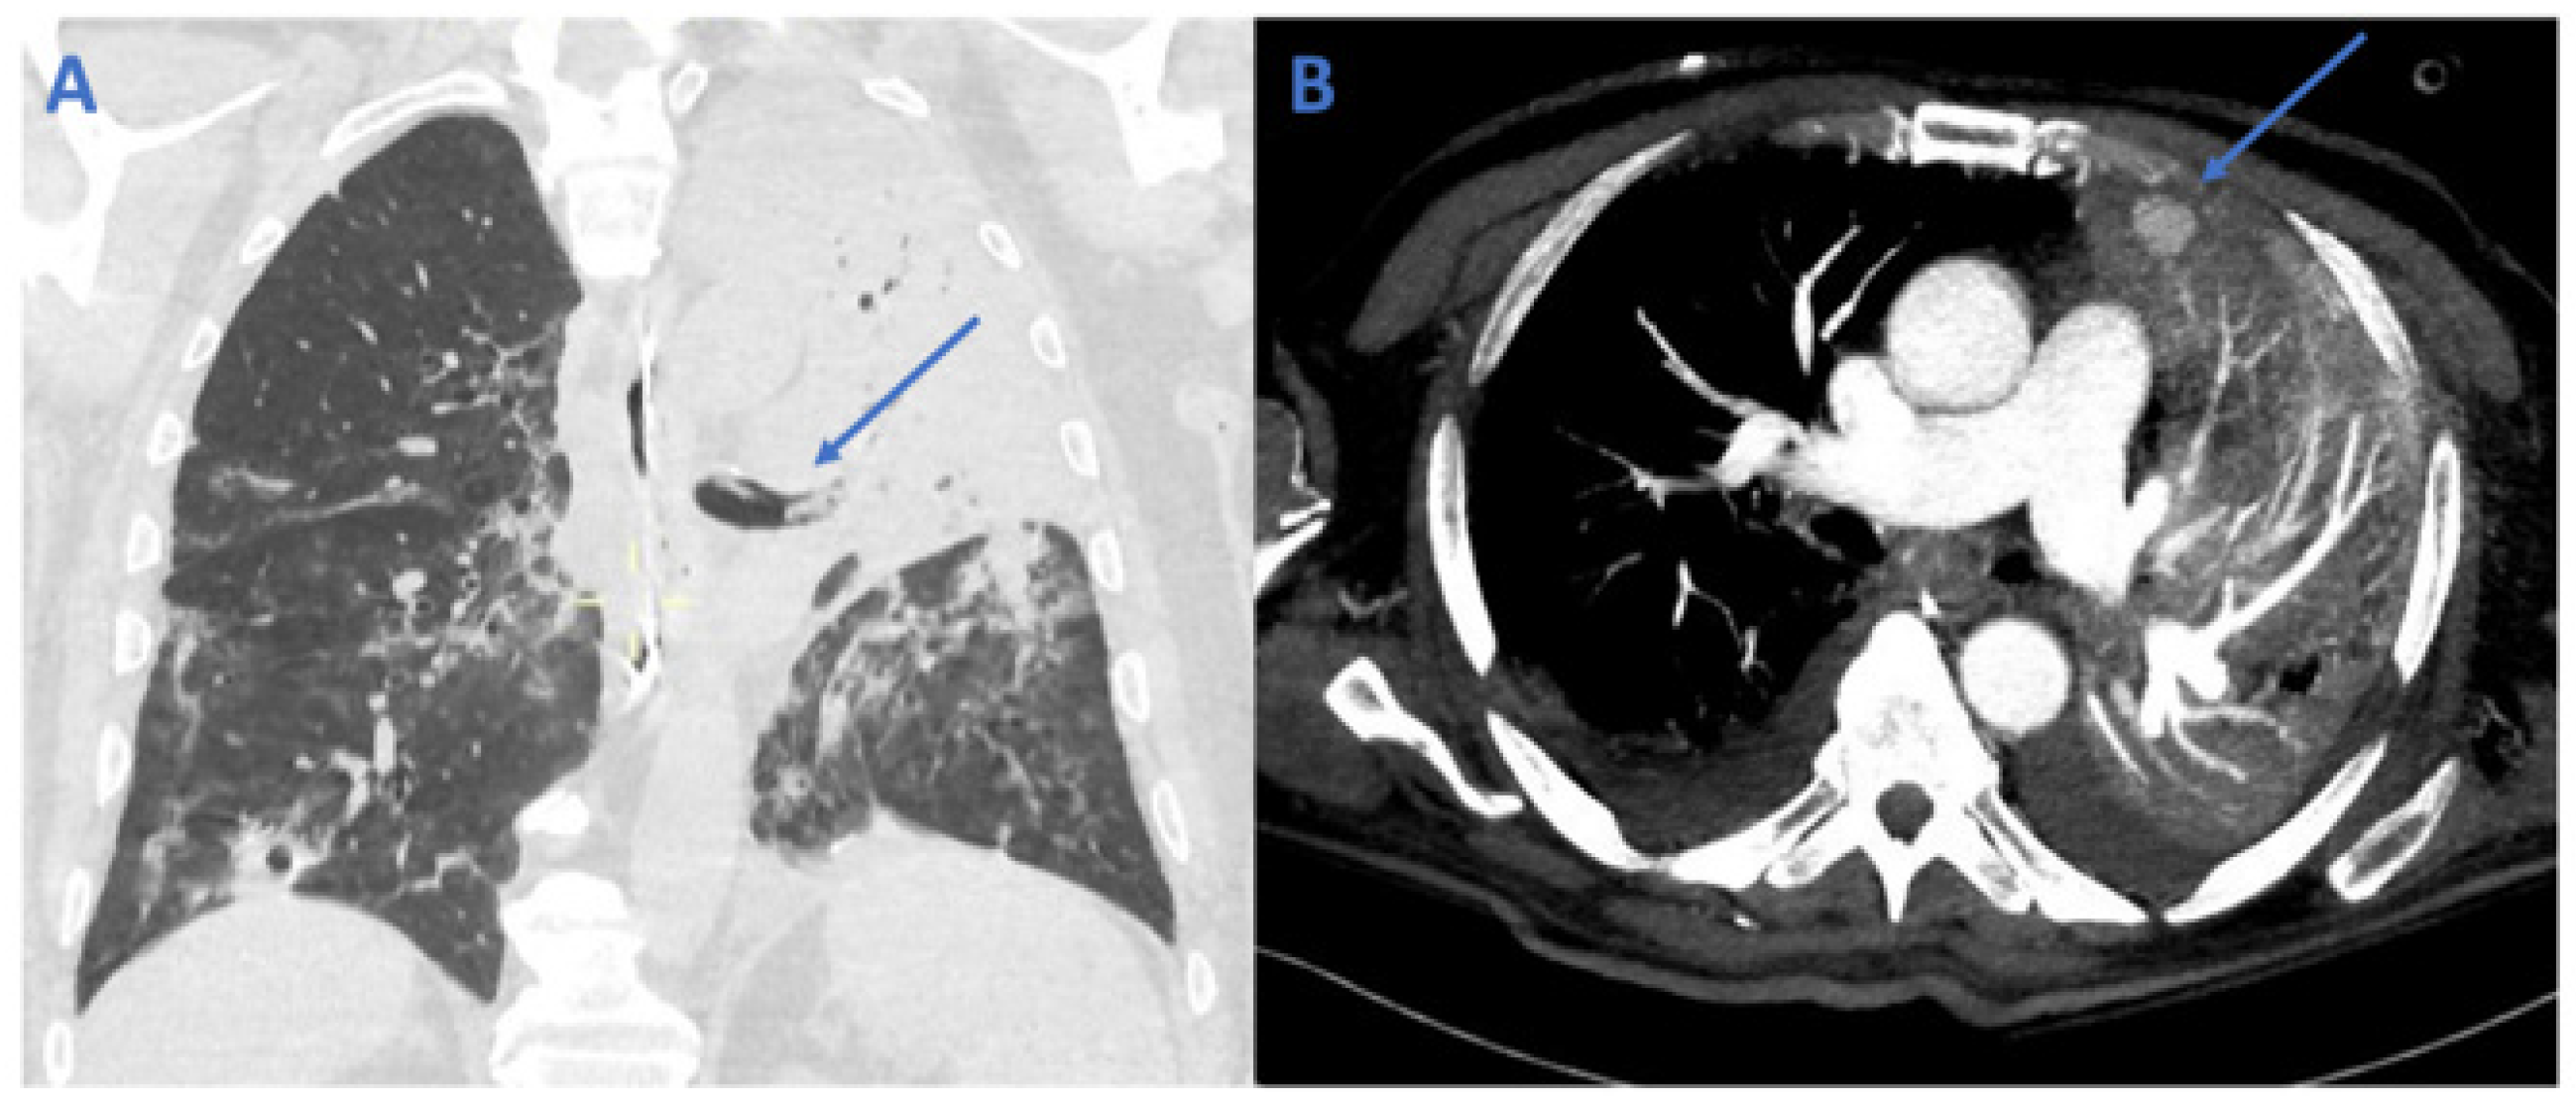

2. Case